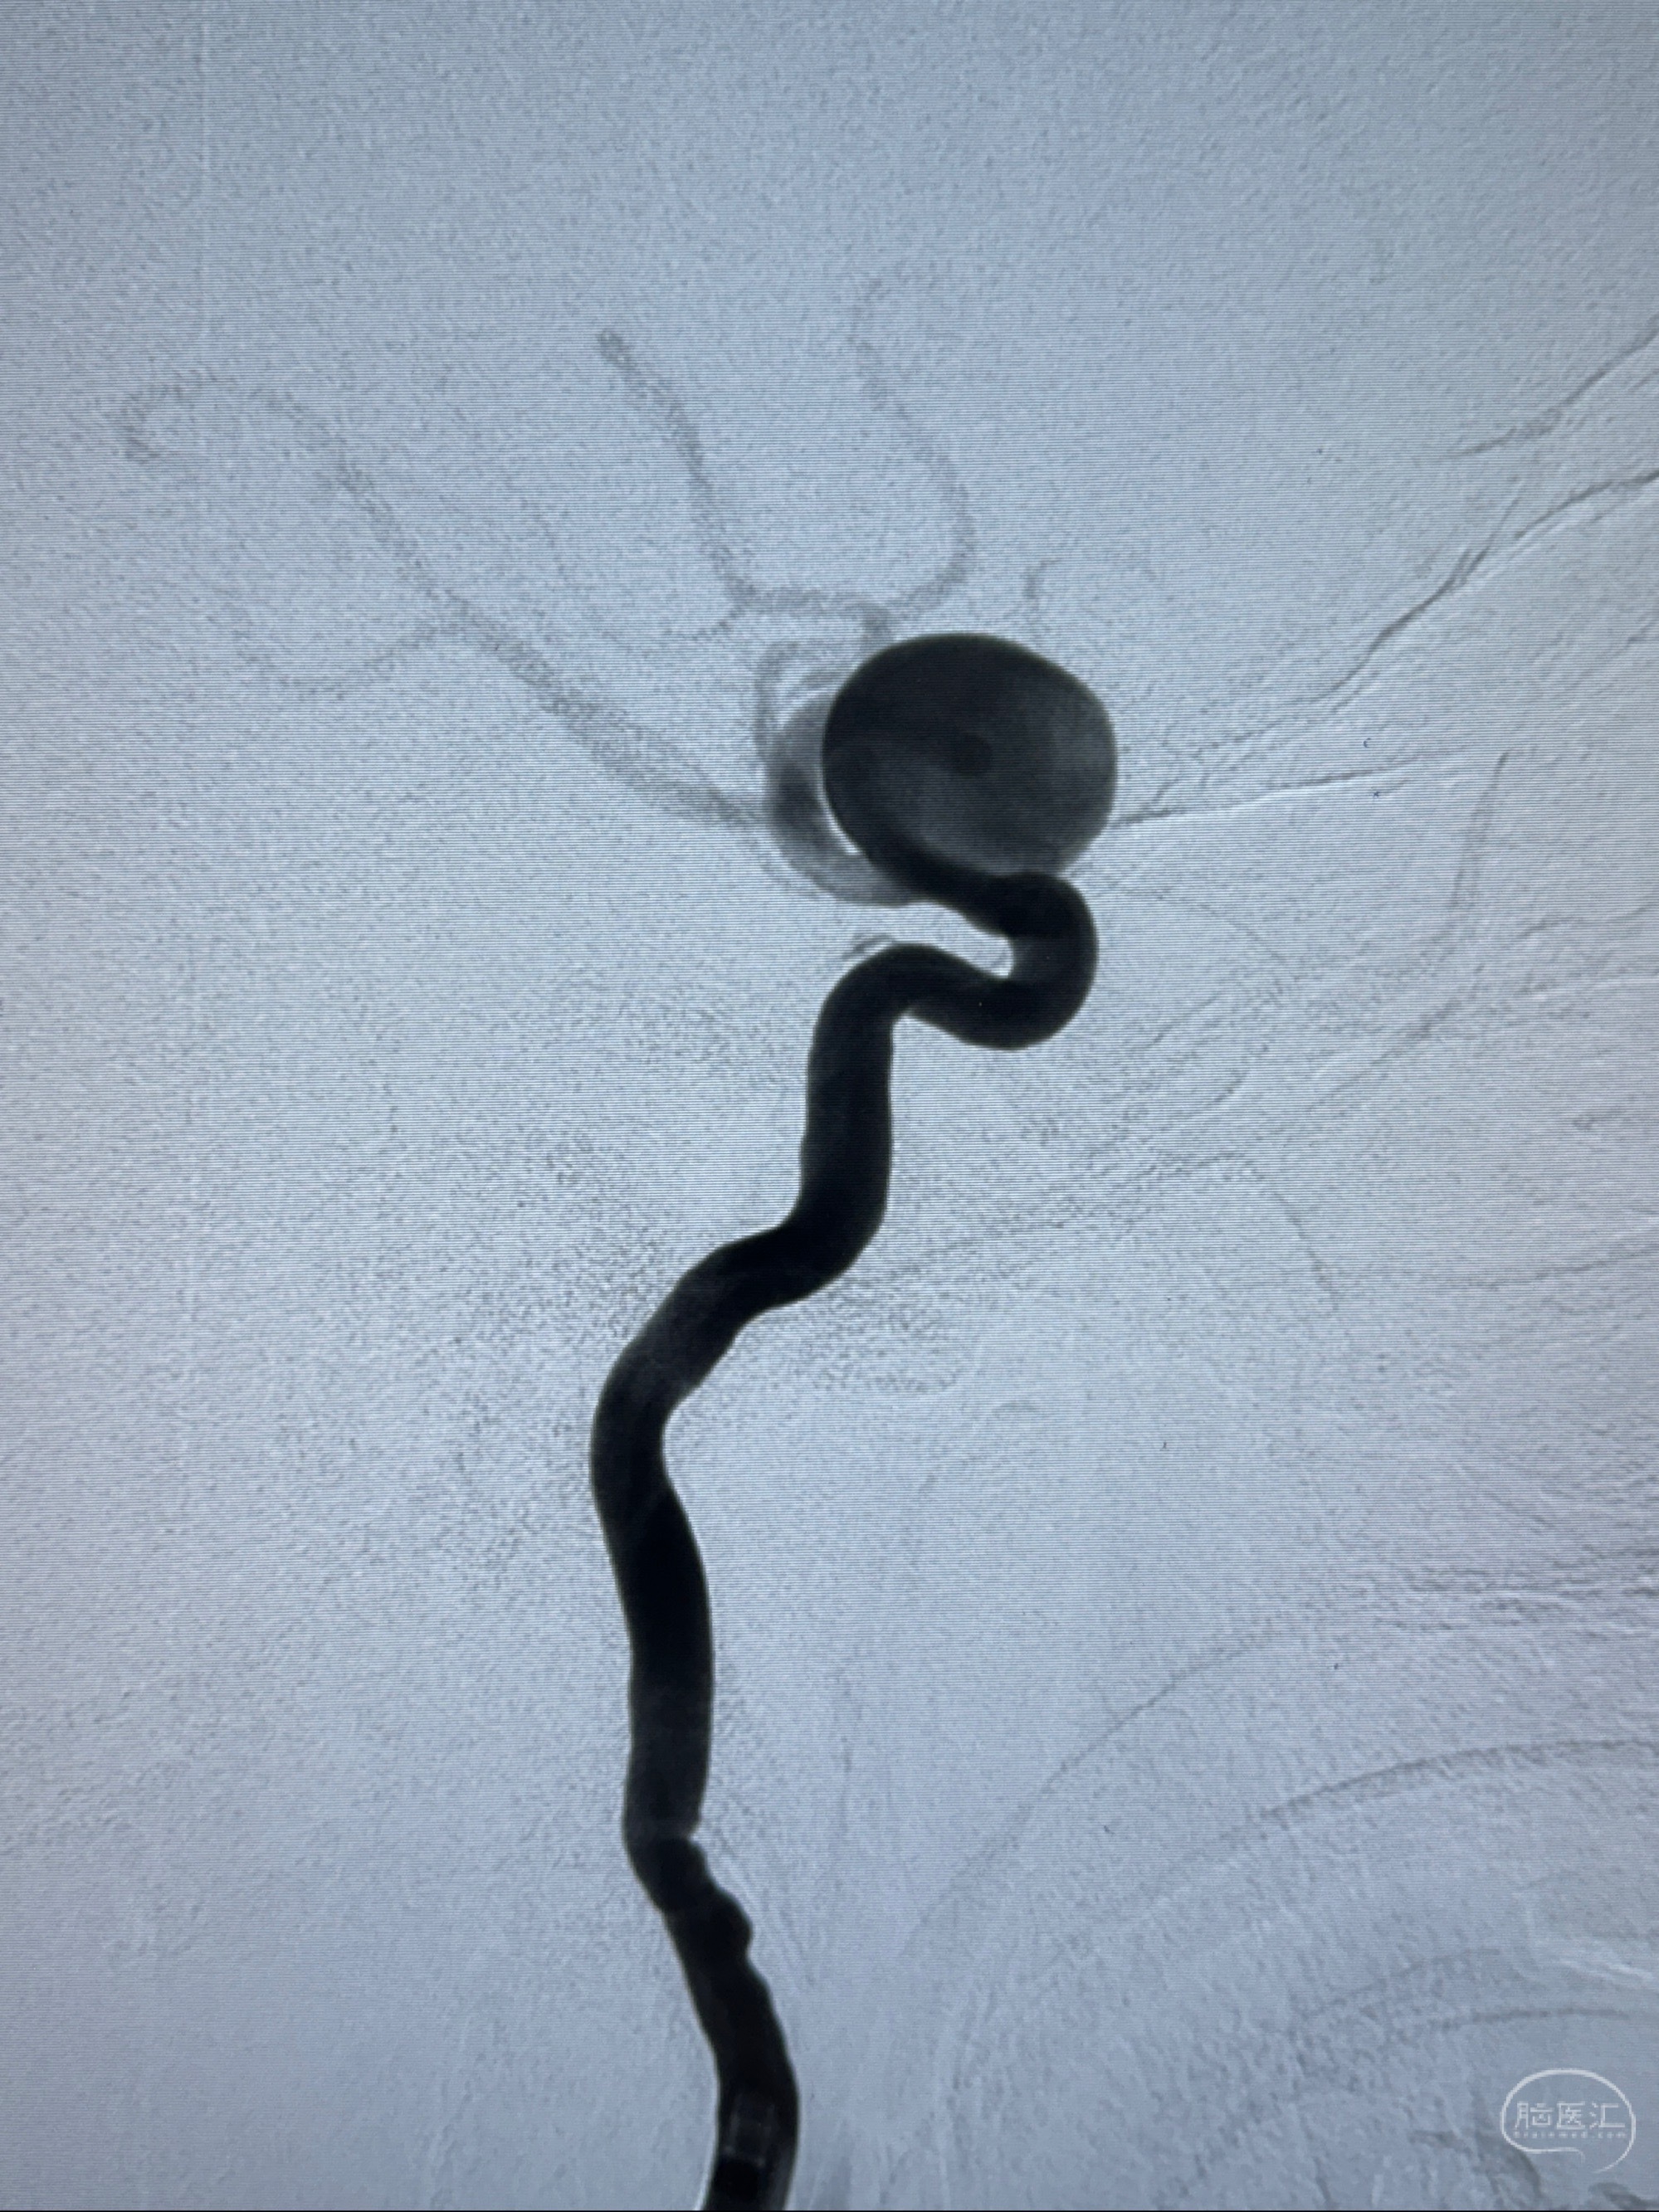

2023-12-08 复旦大学附属华山医院 全脑血管造影:右侧颈内动脉C6段动脉瘤,瘤颈6.68mm,动脉瘤大小13.28*12.34mm

2023-12-08外院DSA:右侧颈眼动脉瘤,约13*12mm大小,压颈试验显示左右向及后向前代偿可

测量动脉瘤的大小:16*13.8*7.6mm大小,较原先变大,考虑双抗后瘤内血栓溶解可能